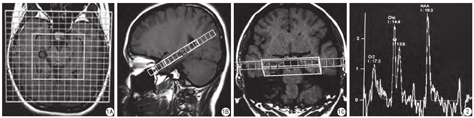

供使用德国Siemens Avanto 1.5 T超导型磁共振扫描仪,多通道相控阵头颅线圈。(1)常规MR成像:行TSE序列T1WI、T2WI及FLAIR横轴面扫描,TSE序列T1WI矢状面扫描,扫描参数如下:T1WI序列,TR 500 ms,TE 9 ms;T2WI序列,TR 4580 ms,TE 112 ms;FLAIR序列,TR 7600 ms,TE 110 ms;矢状面T1WI序列,TR 500 ms,TE 17 ms。以上序列层厚均为6.0 mm,层间隔1.8 mm,矩阵512×256,FOV 230 mm×230 mm,采集次数1。(2)1H-MRS成像:在矢状面上平行于海马长轴行横轴面扫描及垂直于海马长轴行斜冠面扫描,在海马矢状面长轴、海马轴面像及斜冠面上进行定位(图1),以海马为中心范围包含海马头、体、尾部和其外侧的颞叶皮层,MRS扫描采用自动匀场技术,为了获得高质量的波谱图像,定位时需要避开脑脊液和邻近颅骨等组织,并在ROI周围添加饱和带。采用化学位移成像(chemical shift imaging,CSI) 2D多体素(multivoxel,MV)点分辨波谱(point resolved spectroscopy,PRESS)技术进行采集,扫描参数:TR 1500 ms,TE 135 ms,层厚3 mm,间隔1 mm,FOV 230 mm×230 mm,体素大小7.5 mm×10 mm×10 mm,ROI 80 mm×80 mm,扫描时间为7 min 12 s。

将志愿者的原始图像数据传至MMWP工作站,由2名经验丰富的、具有MRS工作经验的放射科医师应用spectroscopy分析软件进行MRS后处理、基线调整、代谢物识别,获取代谢物的波谱图像(图2),测量双侧海马同源对称部位NAA/Cr、Cho/Cr、NAA/(Cho+Cr)值,比值均由计算机自动生成。测量时严格选取海马中轴线两侧同源对称的区域。连续测量三次,取其平均值为最终结果。